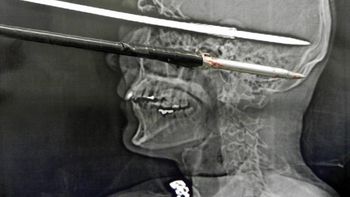

Sin embargo, nadie imaginó que lo peor llegaría al otro día, cuando el sujeto decidió regresar al local para atacar a la mujer. "Volvió con dos palos, uno con un fierro en una de las puntas y el otro con un gancho como de carnicero", contó la damnificada.